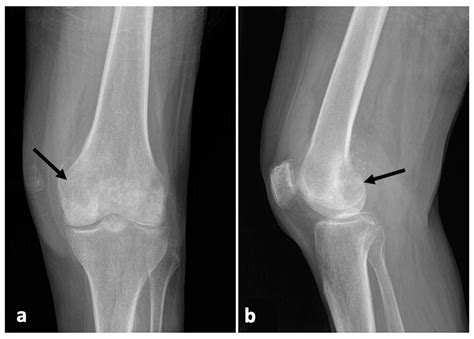

Diagnosing Joint Effusion Knee

Diagnosing joint effusion knee typically involves a combination of physical examination and diagnostic tests. The healthcare provider will:

• Ask about the patient's medical history and symptoms.

• Perform a physical examination of the knee, checking for swelling, tenderness, and range of motion.

• Order diagnostic tests, such as X-rays, MRI, or ultrasound, to visualize the joint and surrounding structures.

• Perform a joint aspiration, where a small amount of fluid is removed from the knee joint using a needle. This fluid can be analyzed to determine the cause of the effusion.